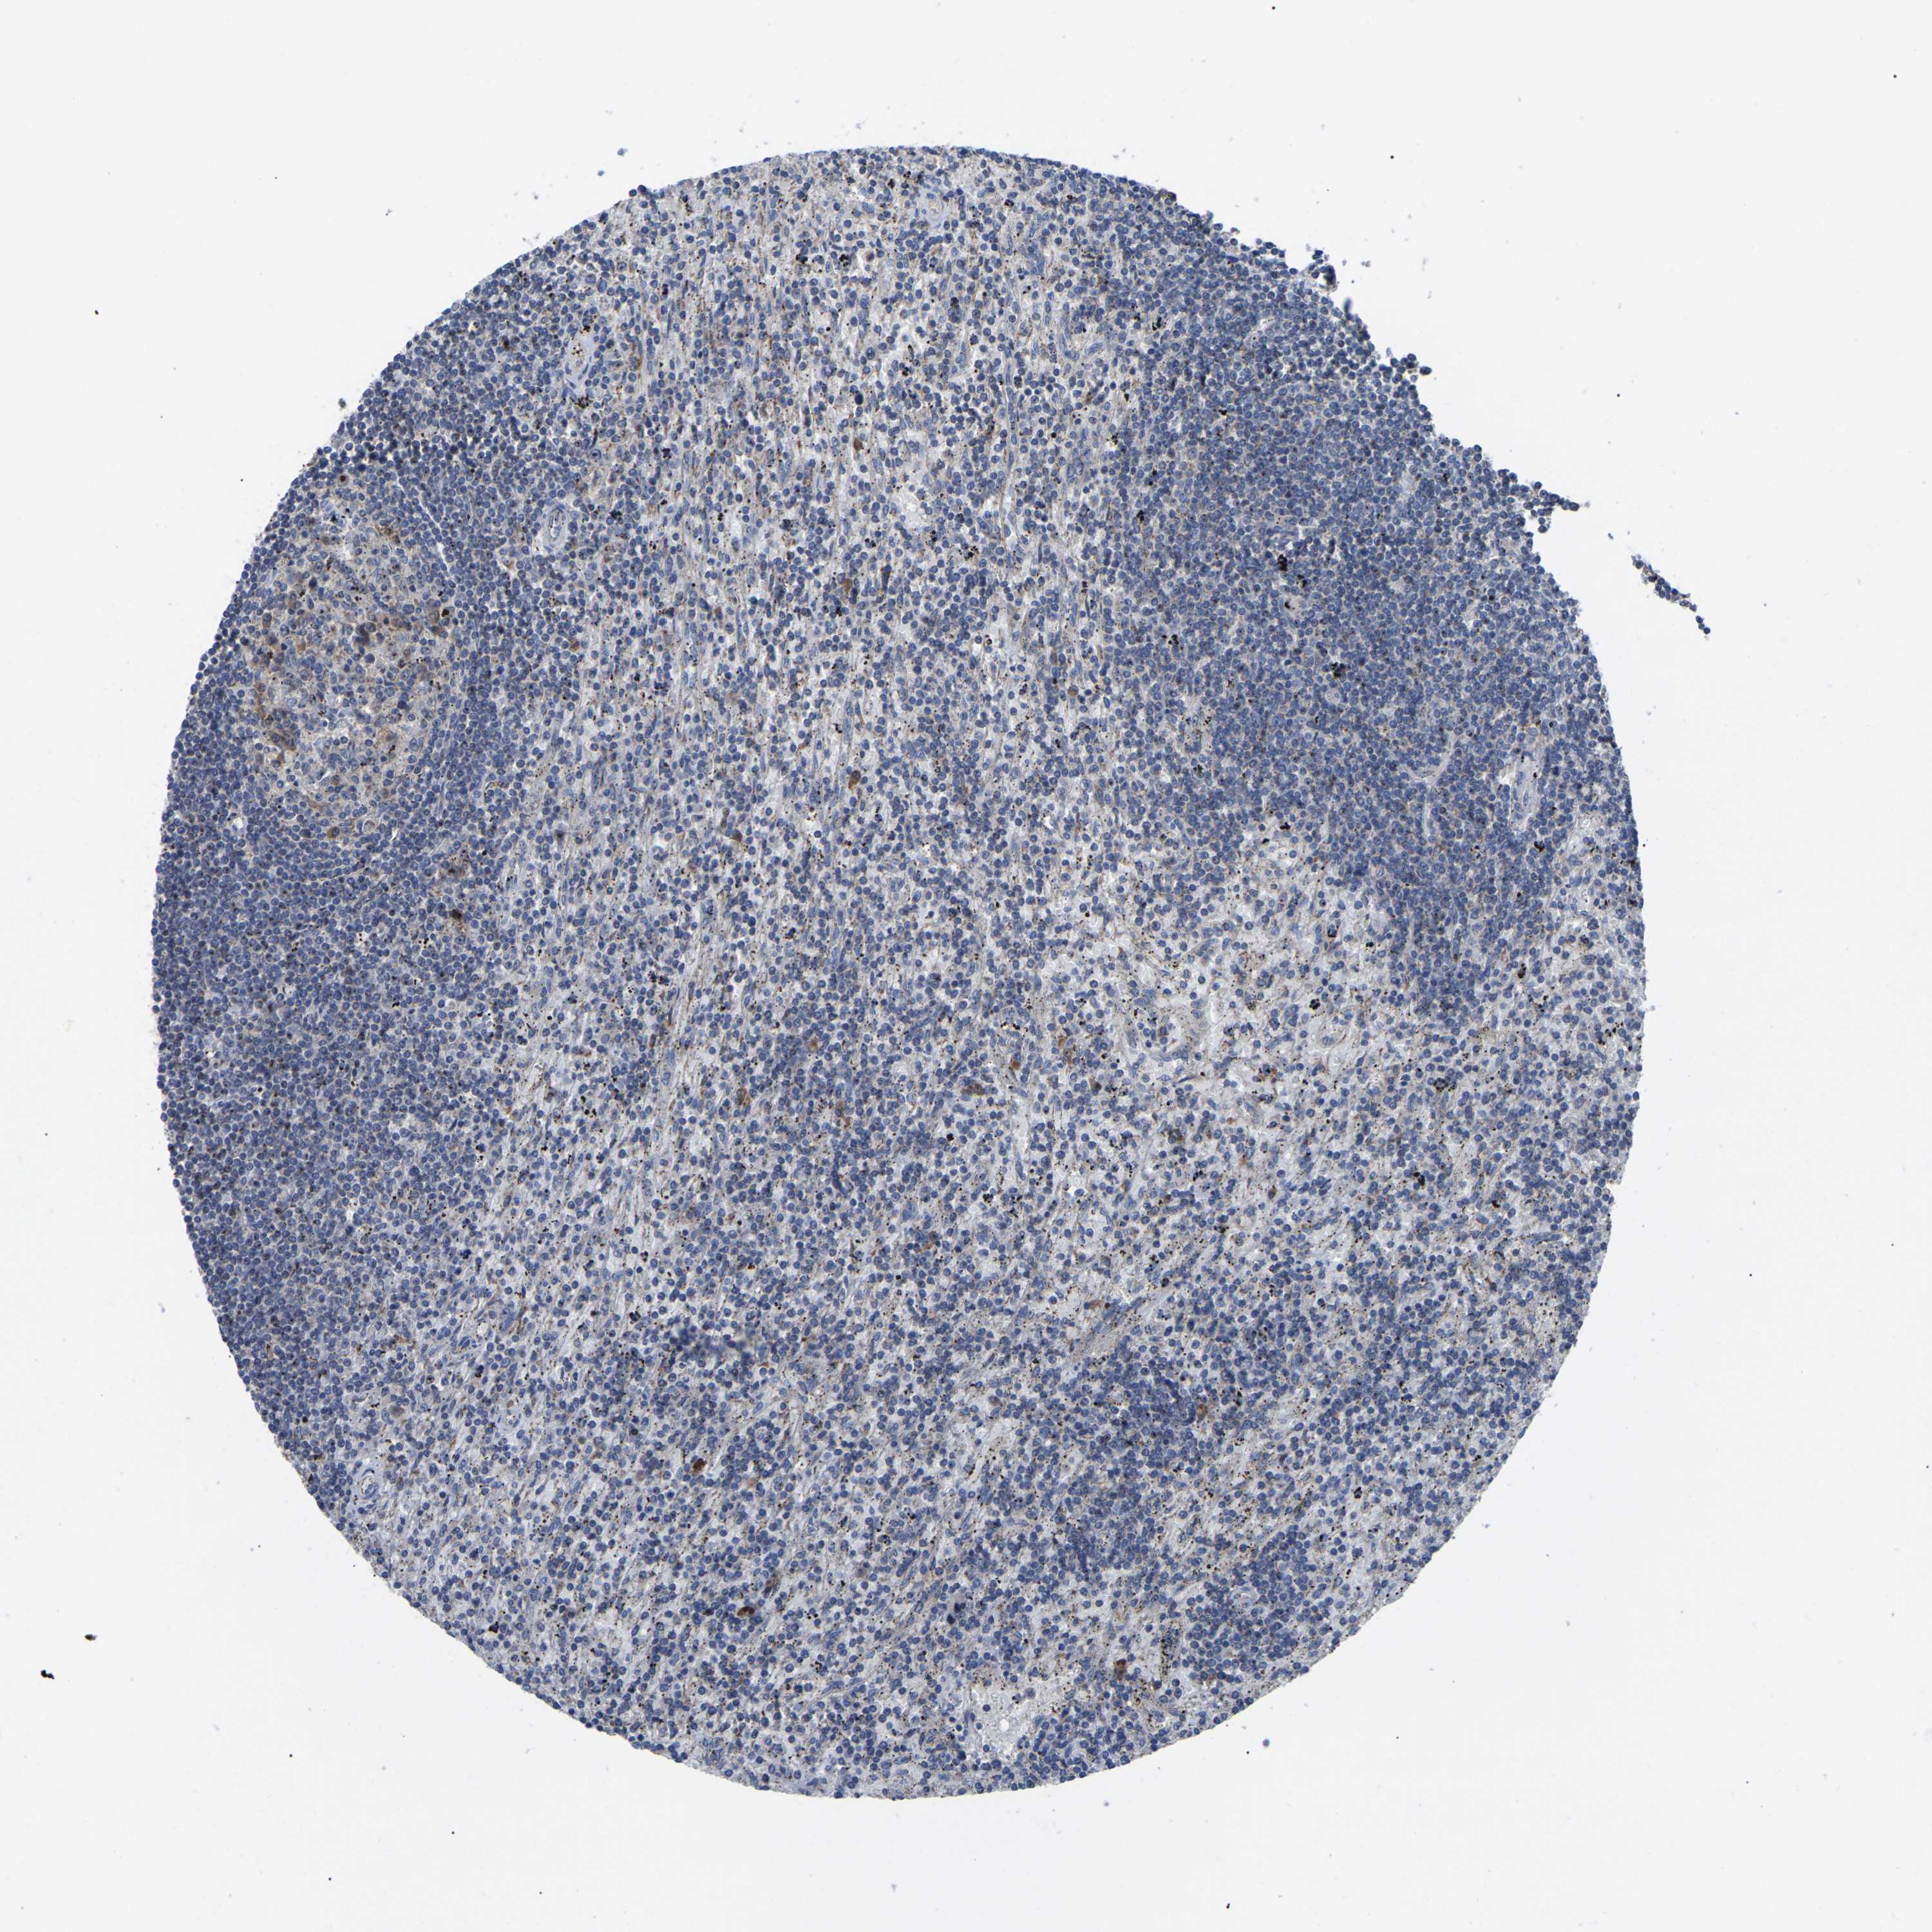

CANCER LYMPHOMA Show tissue menu

LYMPHOMA - Protein expressioni

A mouse-over function shows sample information and annotation data. Click on an image to view it in a full screen mode. Samples can be filtered based on level of antibody staining by selecting one or several of the following categories: high, medium, low and not detected. The assay and annotation is described here.

Each image is clickable and will lead to virtual microscopy that enables deeper exploration of all samples and also displays staining intensity scores, fraction scores and subcellular localization as well as patient and tissue information for each sample.

Antibody HPA018999

Hodgkin's disease, NOS

Malignant lymphoma, non-Hodgkin's type, High grade

Malignant lymphoma, non-Hodgkin's type, Low grade